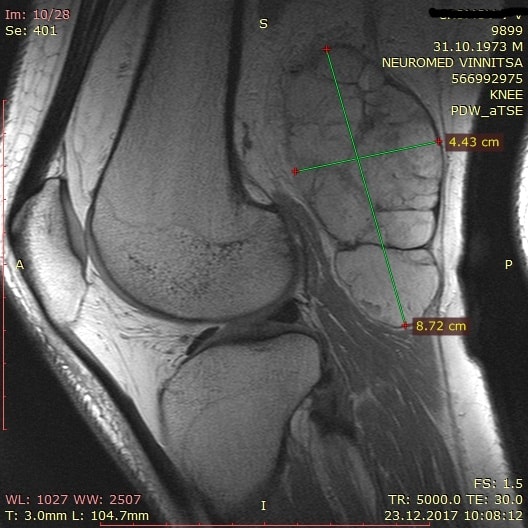

Уважаемые коллеги, подскажите что это может быть. Пациент 44 года, мужчина. 4 месяца назад после незначительной травмы (оступился) начал отмечать незначитеную боль в областе коленного сустава и новообразование в подколенной ямке. Местный травматолог диагностировал кисту бейкера, назначил какие то болтушки и проводил внутрисуставные инъекции "жидкого кислорода"- что это, я так и не понял.

При осмотре - образование в подколенной ямке очень напоминающее кисту бейкера правда на УЗД она мне показалась очень странной - много ячеек и мало жидкости в них - больше ткани чем жидкости, на доплере особого кровотока в кисте я правда тоже не увидел. И незначительная боль при сгибании больше 100 град.

Отправил на МРТ - результат повреждение зад рога мед. мениска штоллер 2 и какое то образование не похоже на кисту и связи с суставом не имеет. Заключение МРТ - синовиома, в чем я лично сомневаюсь.